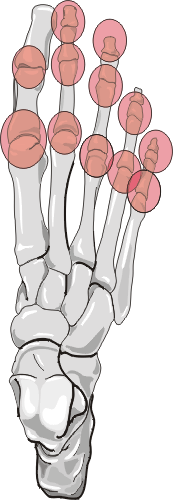

There are three patterns of involvement of psoriatic arthritis in the feet.

First pattern primarily involves DIP, PIP, and MTP. Second pattern is single

ray involvement where all the joints of one digit are involved while other

fingers are spared. The third pattern is similar to rheumatoid arthritis distribution.

Fusiform soft tissue swelling involving a single ray can occur giving the

appearance of 'sausage digit'.

| Joint | Frequency |

| 1st interphalangeal | ++ |

| 2nd - 5th interphalangeal | + | |

| 1st Metatarsophalangeal | +++ |

| 2nd-5th Metatarsophalangeal | +++ |

| Tarsometatarsal | - |

| Chopart | - |